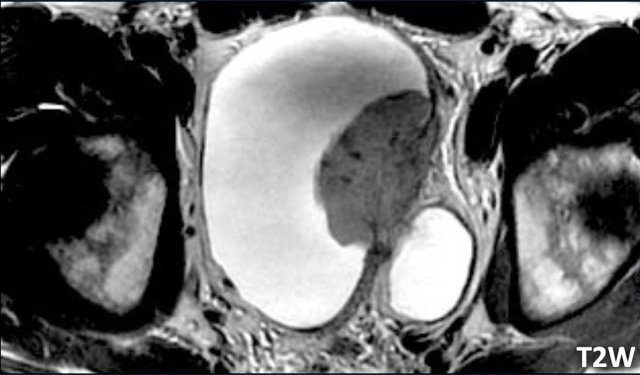

Image

There is a large papillary tumor on the left lateral bladder wall which infiltrates the hypointense line of the muscularis propria.

This is a difficult case to evaluate, as it looks like there is fat infiltration.

However T2W-images wiIl frequently overestimate fat invasion due to partial volume.

The next step is to study the DCE and diffusion images to differentiate between VI-RADS 4 and 5.

The DCE and DWI images will differentiate between VI-RADS 4 and 5.